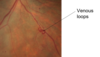

[The light reflex can be seen in the image attached - it is the light white stripe across the blood vessel when you look closely]

[In the image attached focus on the S shape made]